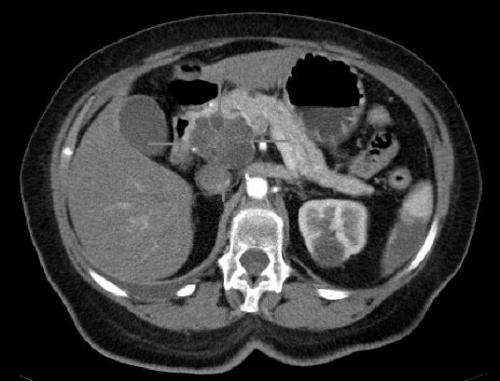

軸向CT圖像,靜脈造影。胰頭大囊性腺癌。